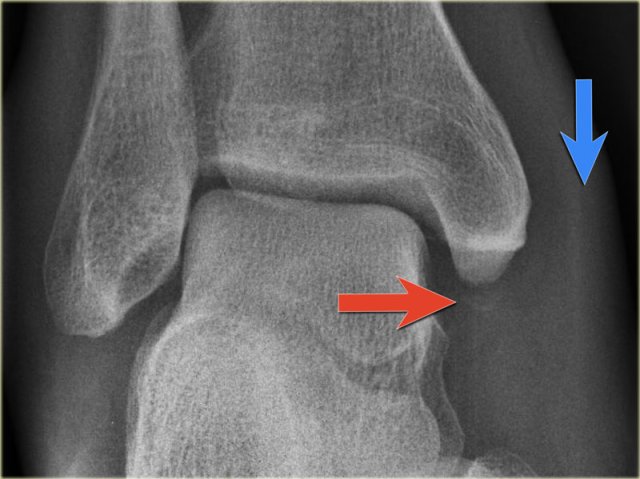

PE stage 1 PE stage 1

• Re-examination

On the ankle films there was no sign of an oblique fracture of the lateral malleolus, so we can exclude a Weber B fracture.

There is still the possibility of a Weber C fracture stage 4, i.e. medial rupture or avulsion, high fibular fracture and finally a posterior malleolus fracture.

At reexamination you notice the subtle avulsion of the medial malleolus (red arrow), which is stage 1.

Notice also the soft tissue swelling on the medial side (blue arrow)

PE stage 3 PE stage 3

Additional radiographs of the lower extremity were ordered and they demonstrate a high fibular fracture, i.e. Weber C stage 3 also known as a Maisonneuve fracture.

• Final report

Weber C fracture stage 4.

This is un unstable ankle injury that needs surgical repair.